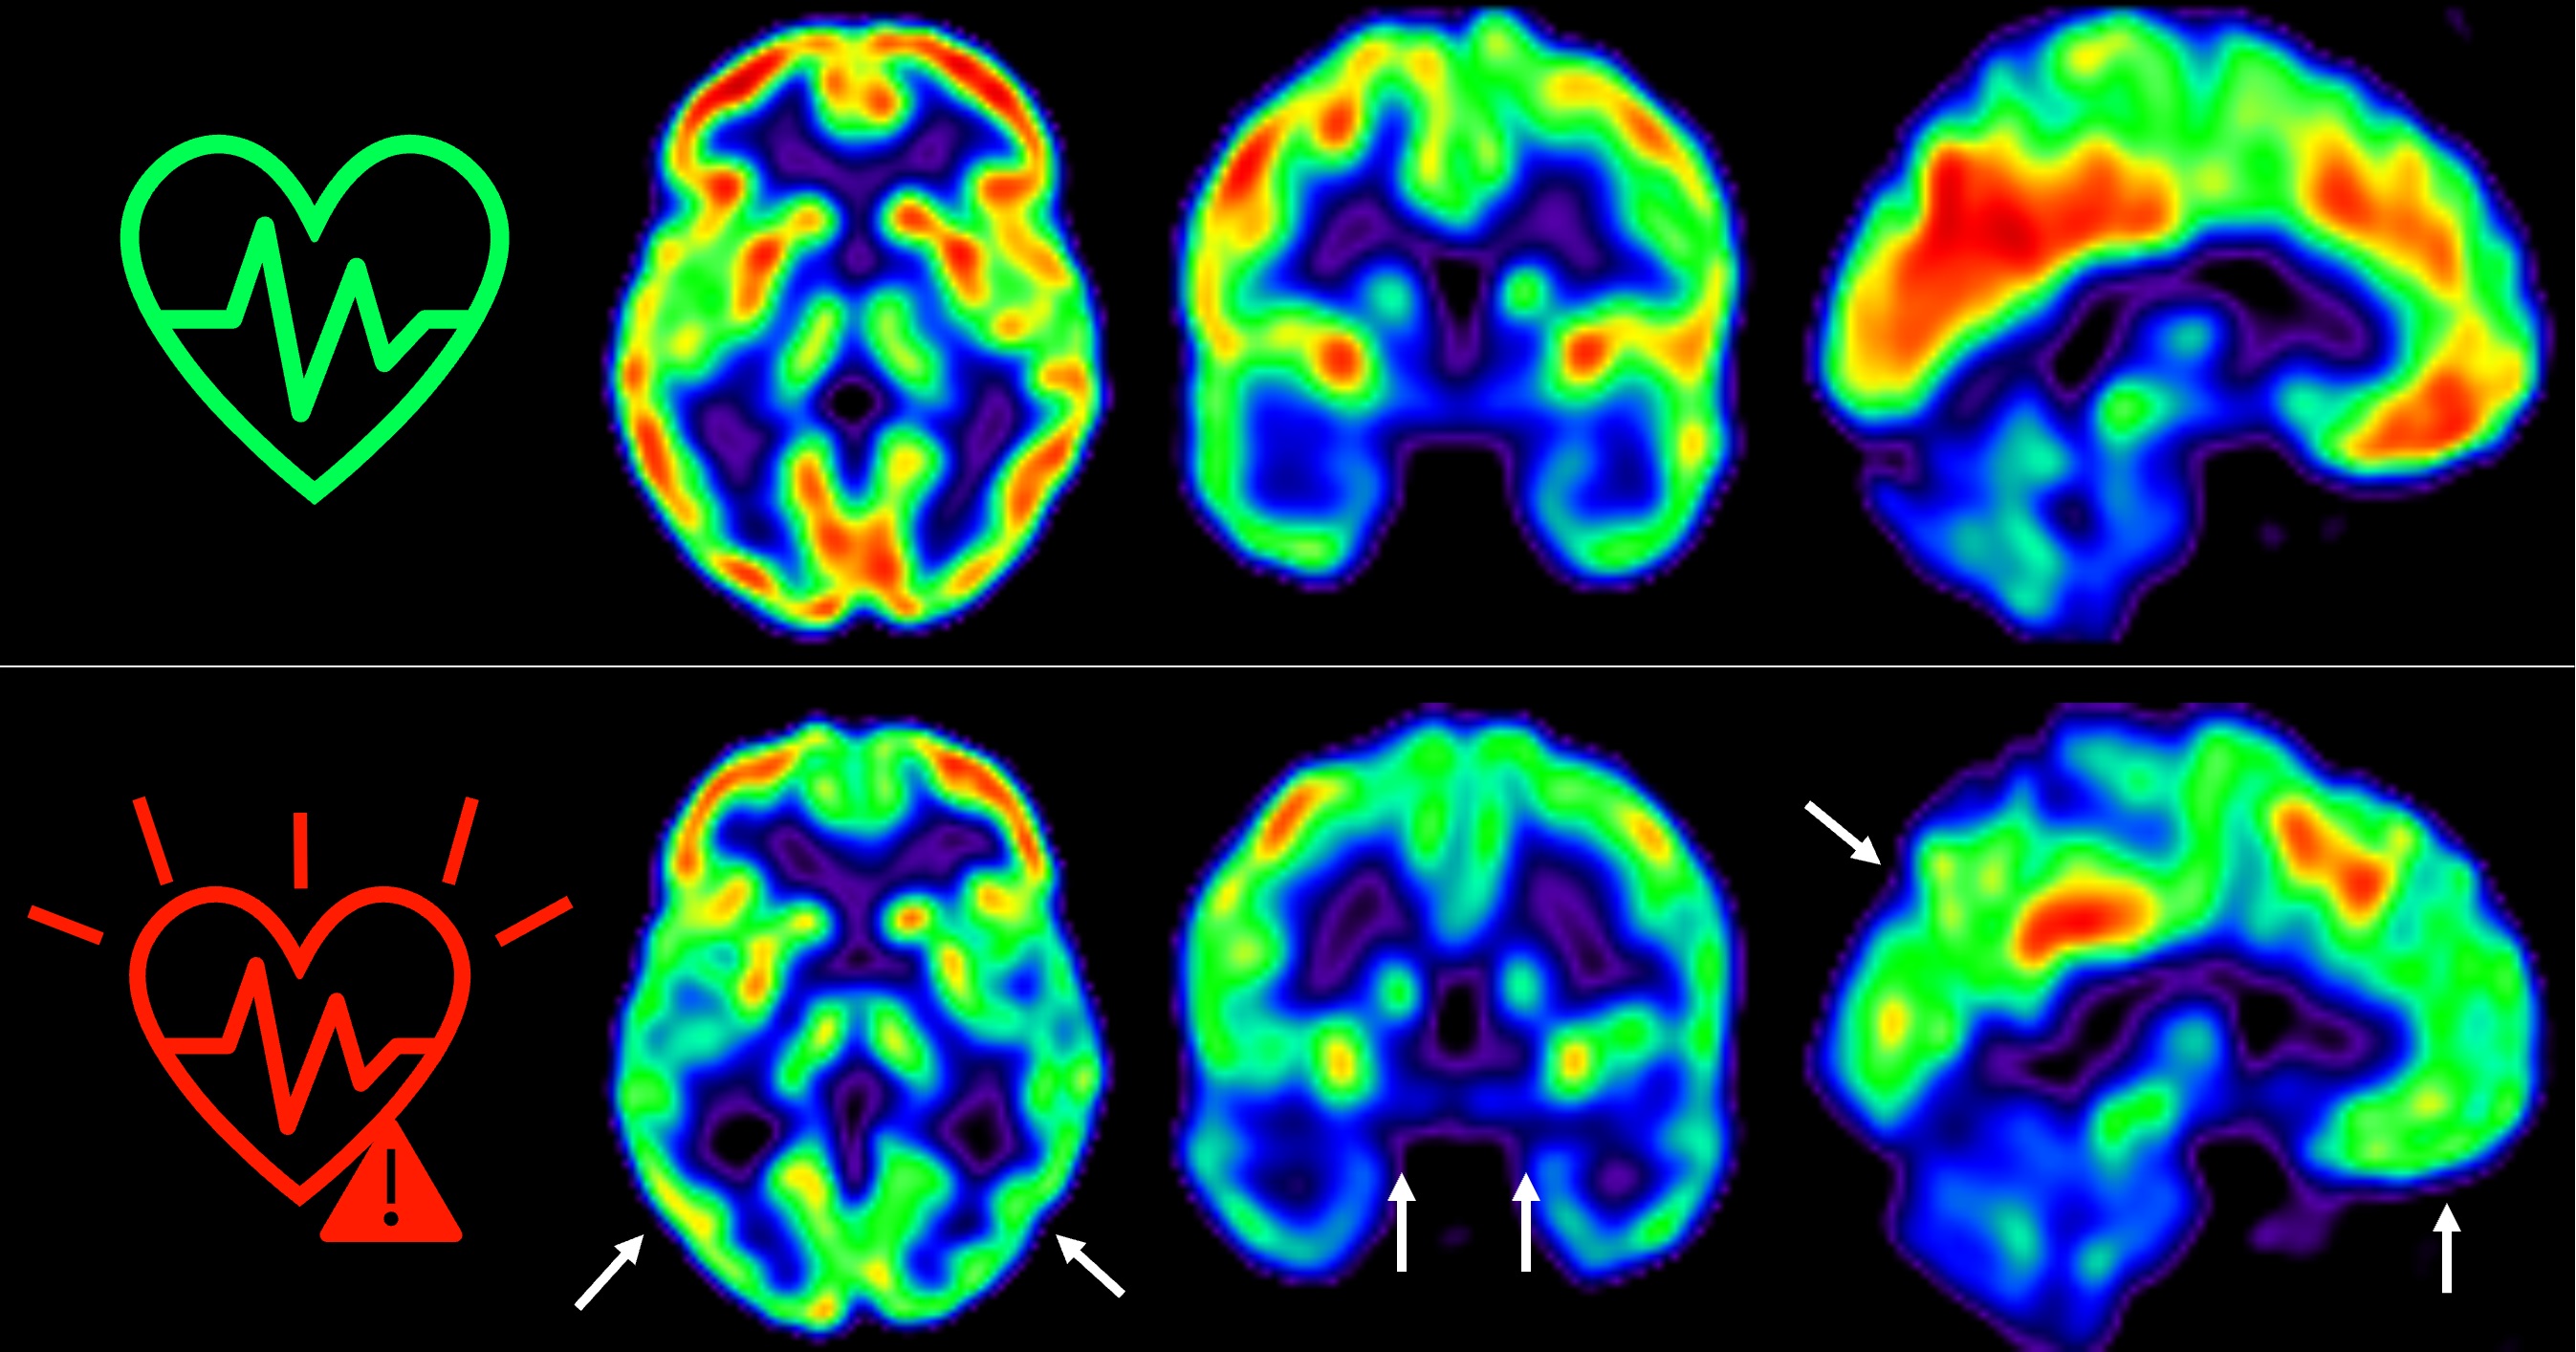

El equipo, liderado por los Drs. Marta Cortés Canteli y Juan Domingo Gispert, ha seguido a estos individuos a lo largo de 5 años y han encontrado que aquellos que mantienen un riesgo cardiovascular elevado durante todo este tiempo sufren una disminución aún mayor del metabolismo cerebral medido a través de técnicas de imagen como tomografía por emisión de positrones (PET).

Hemos detectado un declive metabólico cerebral tres veces mayor que el de personas que se mantienen en bajo riesgo cardiovascular”, señala Catarina Tristão-Pereira, primera firmante del artículo y becaria INPhINIT de la Fundación ”la Caixa.

Además, el equipo descubrió que la progresión de la aterosclerosis subclínica en las carótidas durante estos 5 años se relacionaba con una disminución del metabolismo en regiones cerebrales vulnerables a la enfermedad de Alzheimer, de manera aditiva al efecto de los propios factores de riesgo cardiovascular. “Estos resultados corroboran que la detección por imagen de la aterosclerosis subclínica aporta información muy relevante”, añade el Dr. Fuster, investigador Principal del estudio PESA. “La relación entre el cerebro y el corazón es un tema fascinante y con este estudio hemos visto que empieza mucho antes de lo que se creía”, continúa.